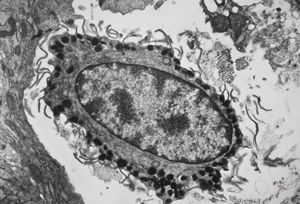

M,11y. | mast cell - skin